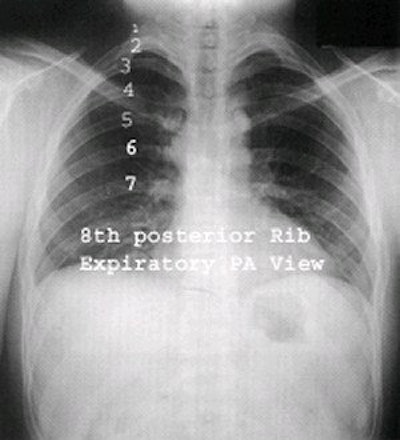

Variations

An expiratory film may be helpful under some circumstances. A small pneumothorax (air in the pleural cavity) may be difficult to detect on a routine inspiratory PA film. On expiration, the volume of the thorax and lungs is reduced but the amount of air in the pleural space remains essentially unchanged. The pneumothorax then occupies a larger percentage of the area of the thorax and is more easily visible.

Another indication for an expiratory film is to demonstrate air trapping. The bronchi increase in diameter with inspiration, and decrease with expiration. With a foreign body or tumor in a main bronchus, a valve action may occur, with air bypassing the obstruction on inspiration and becoming trapped on expiration.

Expiration PA view. Image courtesy of Dr. Naveed Ahmad.

With expiration, the normal lung is reduced in volume and becomes more radiopaque. The obstructed portion of the lung retains its air, thereby retaining its radiolucency and forcing the mediastinum to shift toward the contralateral side. If a patient has a unilateral respiratory wheeze, air trapping is likely, and an expiratory film may be helpful.